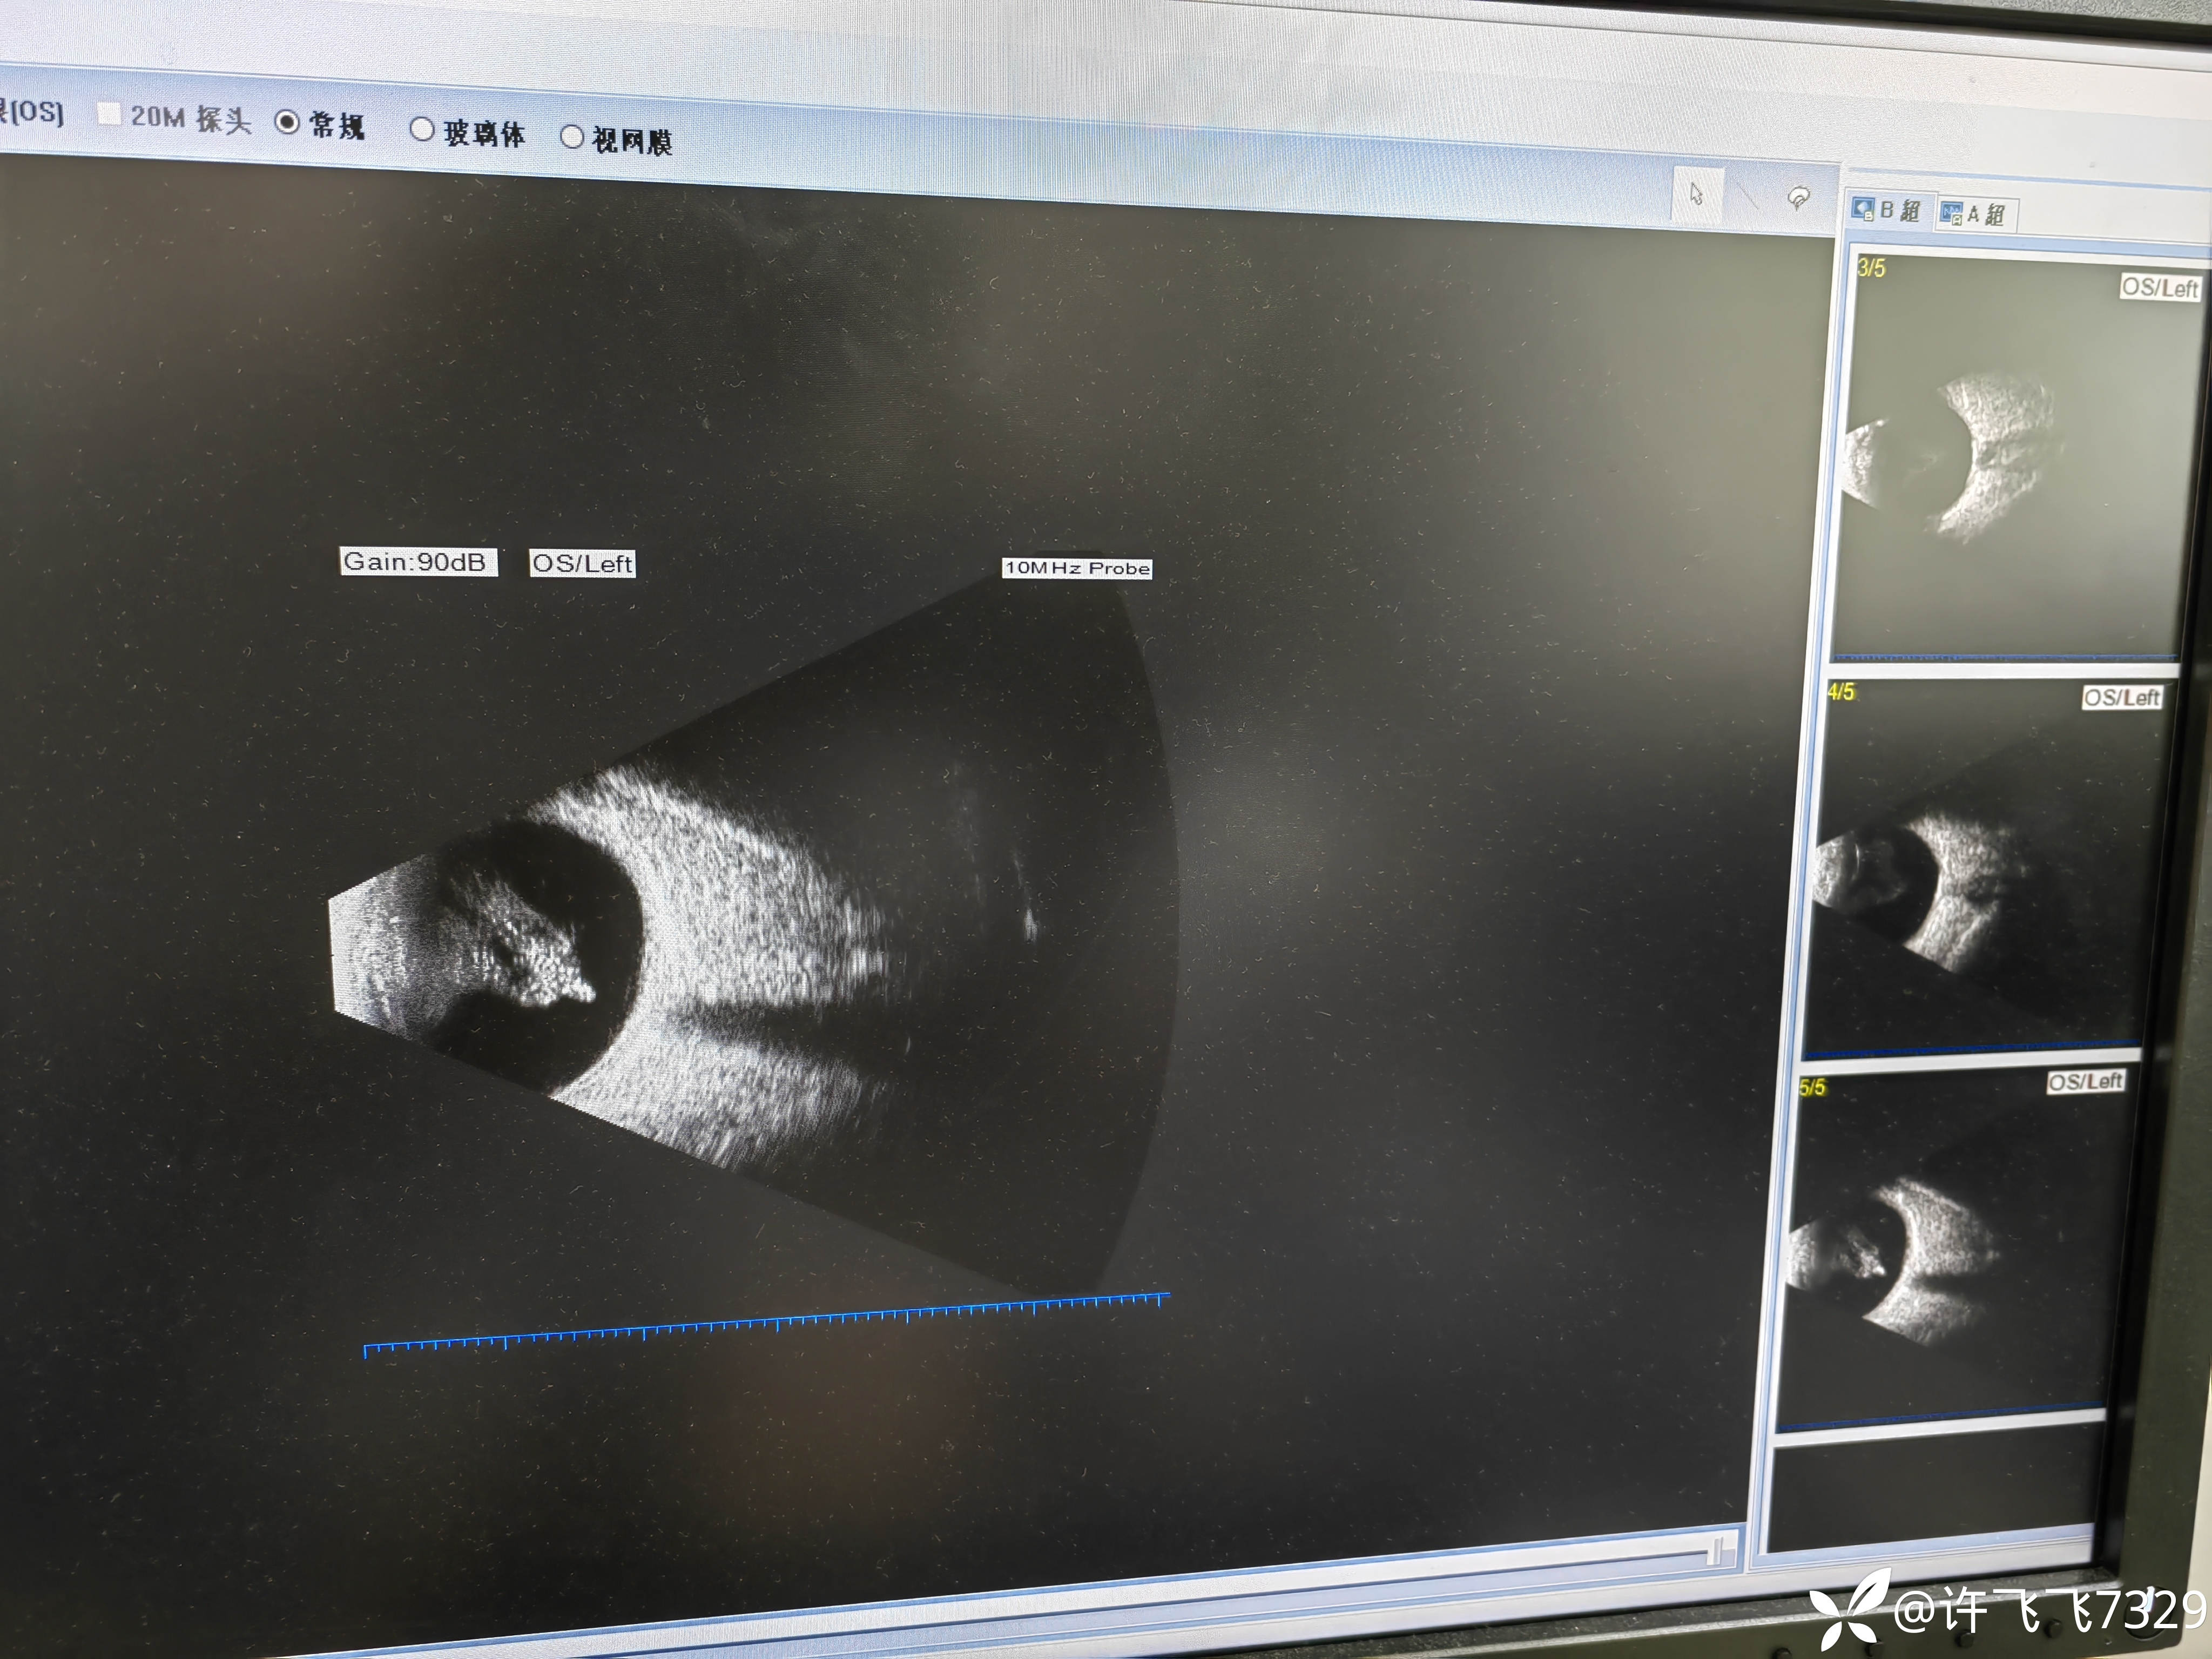

左眼视物不清十年余

【患者信息】:85岁老年女性

【主诉】左眼视物不清十年余

【现病史及既往史】:左眼青光眼手术十年余,右眼青光眼

【临床诊断】:双眼老年性白内障,双眼青光眼

【治疗经过及结果】:初干眼科的小白,眼科各位大佬们,这B超里面是玻血吗?这是什么东西?